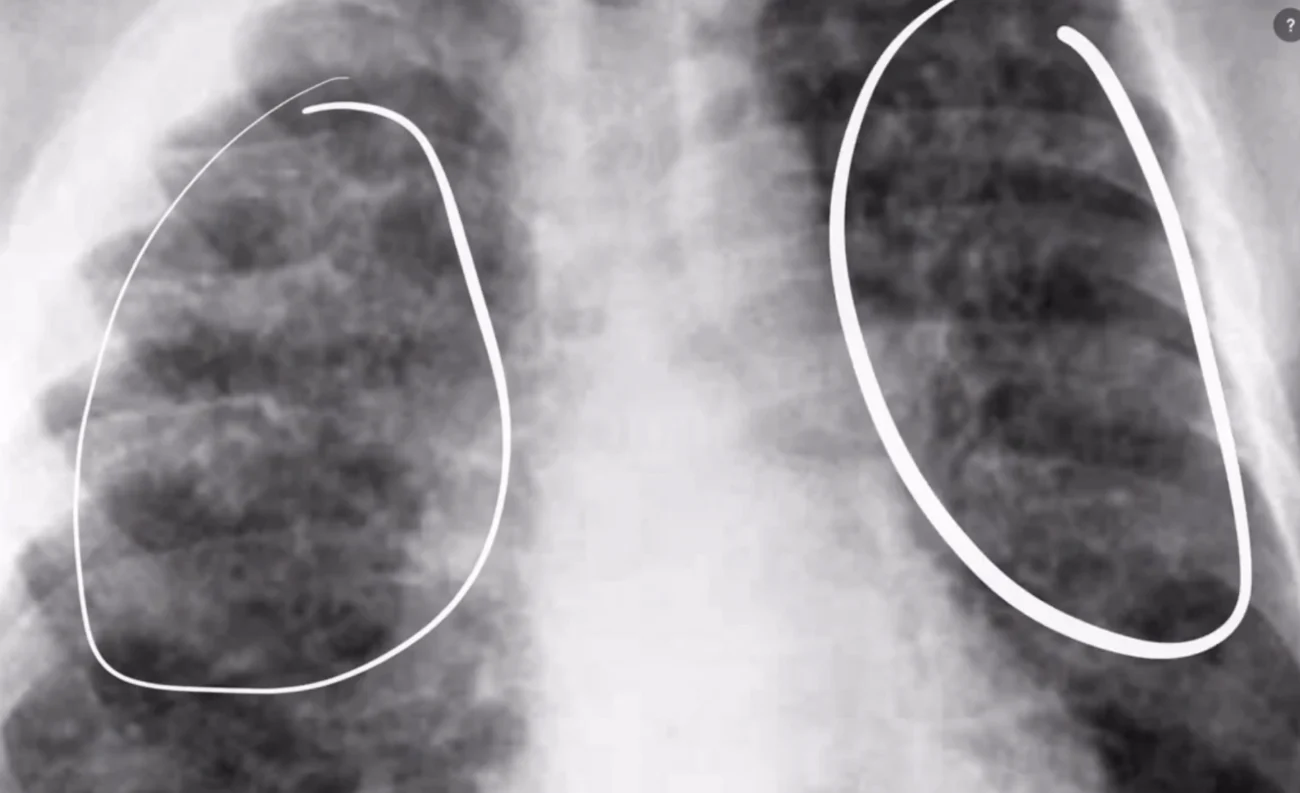

Instead of a solid white consolidation, atypical pneumonia often produces a fine, hazy, or ground-glass appearance on the X-ray. The lung looks like it has a diffuse haziness or a slight whitening spread across a large area, rather than one solid white patch. During the COVID-19 pandemic, the characteristic X-ray appearance of COVID-19 pneumonia became one of the most recognized imaging patterns in radiology — typically showing bilateral, peripheral, and lower-zone predominant ground-glass opacities.

Appearances of atypical pneumonia on X-ray:

Diffuse haziness or ground-glass opacity

Bilateral involvement (both lungs affected)

Reticular (net-like) pattern from interstitial inflammation

Less well-defined than lobar consolidation

May look deceptively mild on X-ray even when the patient feels very ill